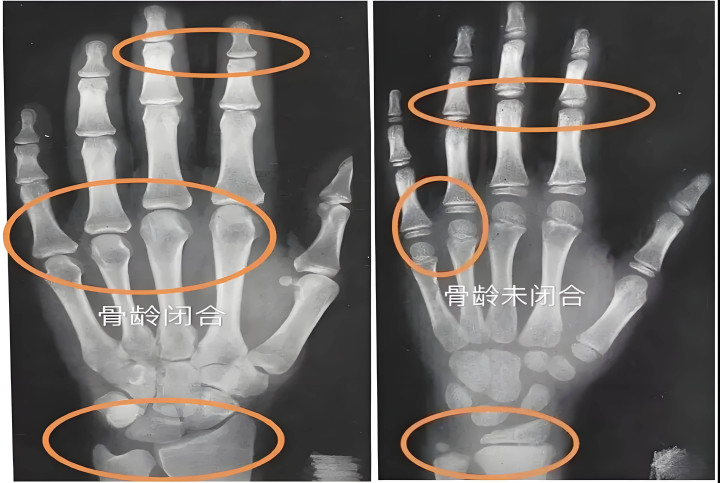

在这一阶段,生殖系统开动发育,深广激素分泌,促使长骨骨骺快速增殖。由于骨骼发育存在“不成逆性”,一朝骨骺线闭合,无论接收何种外部时刻,身高皆将罢手增长。

身高的加多本色上是长骨(如股骨、胫骨)长度的加多。在长骨的结尾,有一层特等的软骨组织,被称为“骨骺线”。

在孕育激素和胰岛素样孕育因子(IGF-1)的作用下,骨骺软骨细胞不休辩别、增殖、骨化,从而使骨头向两头蔓延。

闭合逻辑:跟着芳华期的股东,性激素(雌激素和雄激素)水平升高。性激素一方面在初期会促进孕育激素的分泌,导致“蹿个儿”;但另一方面,星空体育官网它也会加快骨骼的训练。当性激素水平达到一定阈值,骨骺软骨会透顶骨化,骨骺与干骺端竣工会通,生漫空间消失。

操作:带孩子去病院拍摄左手腕骨X光片。

逻辑:骨龄反应了骨骼真正的训练进度。如若骨龄比推行年级大越过1岁,证明发育提前,孕育周期被压缩;如若骨龄落伍,则可能存在孕育激素阑珊或其他代谢问题。